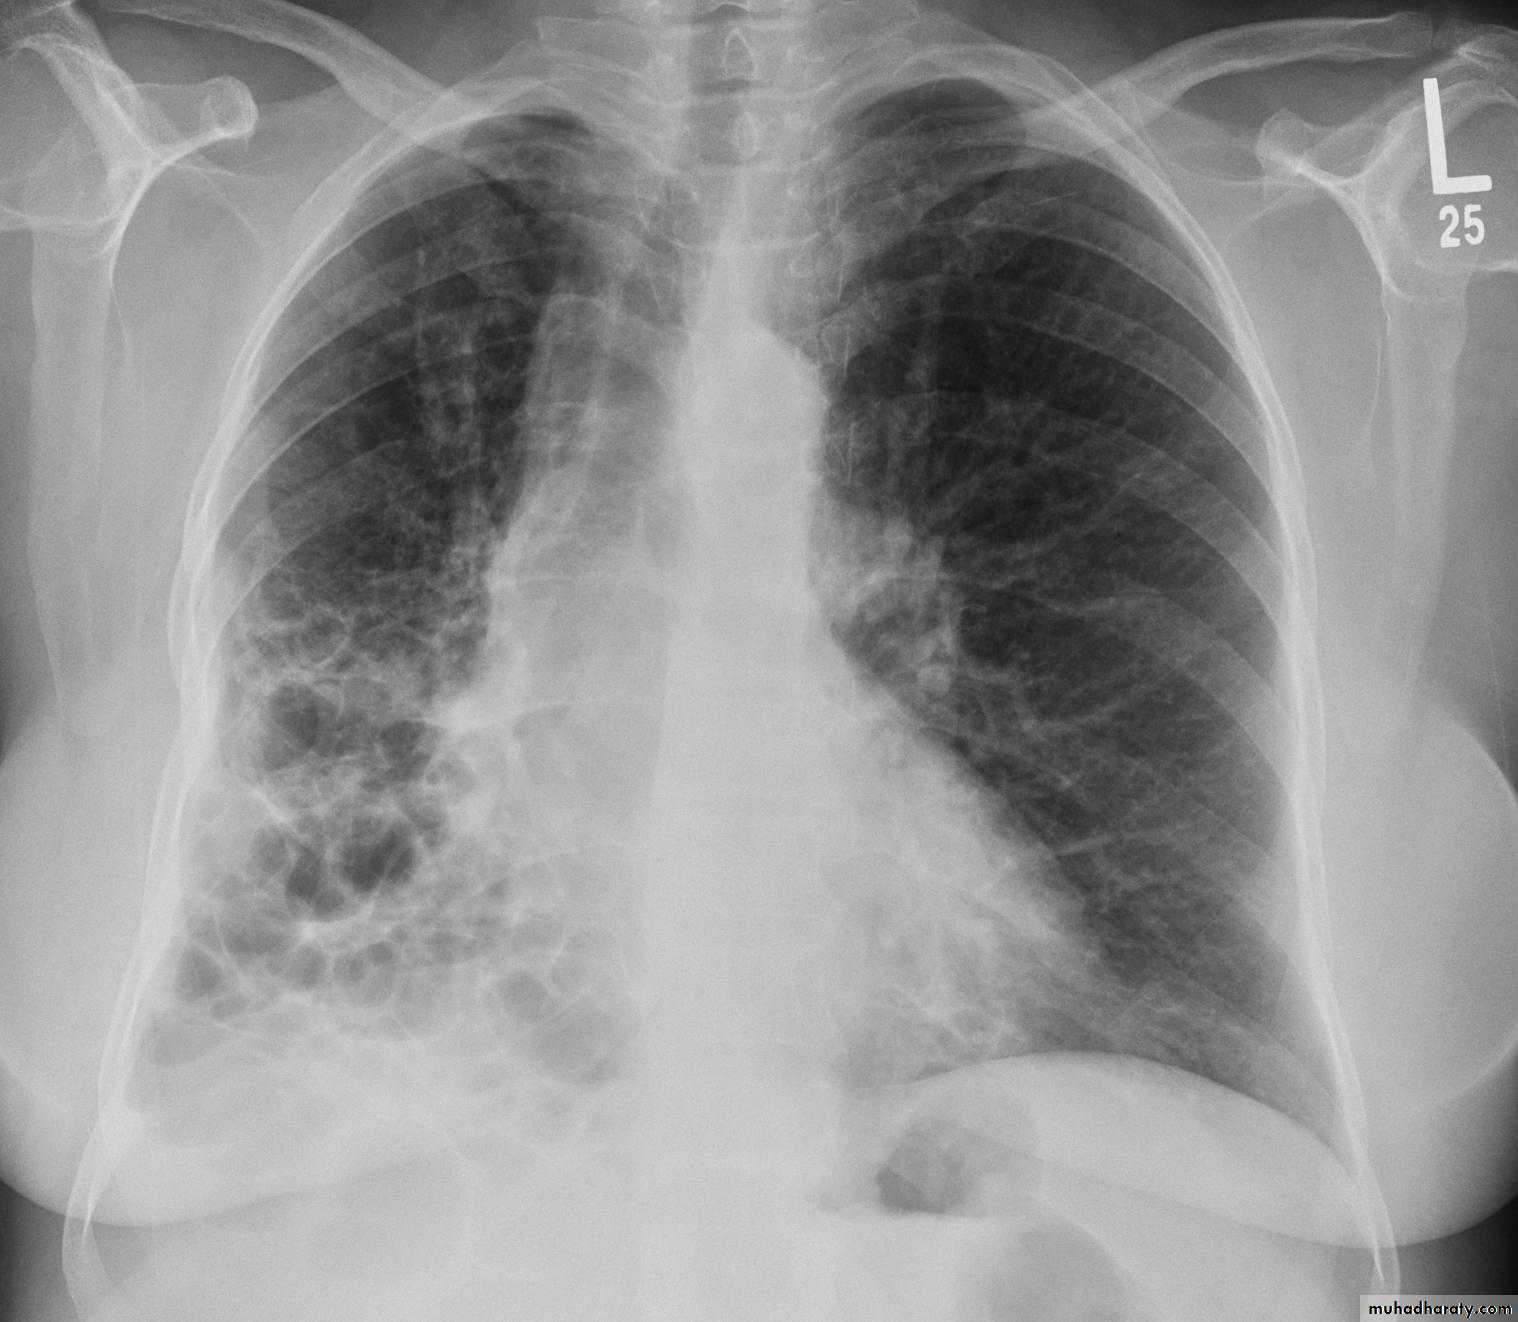

Miliary shadow

1) infection ( TB ,fungal , viral )2)Dust inhalation (workers in dust materials)

3) Metastasis

=2-3mm

After treatment

Miliary TB